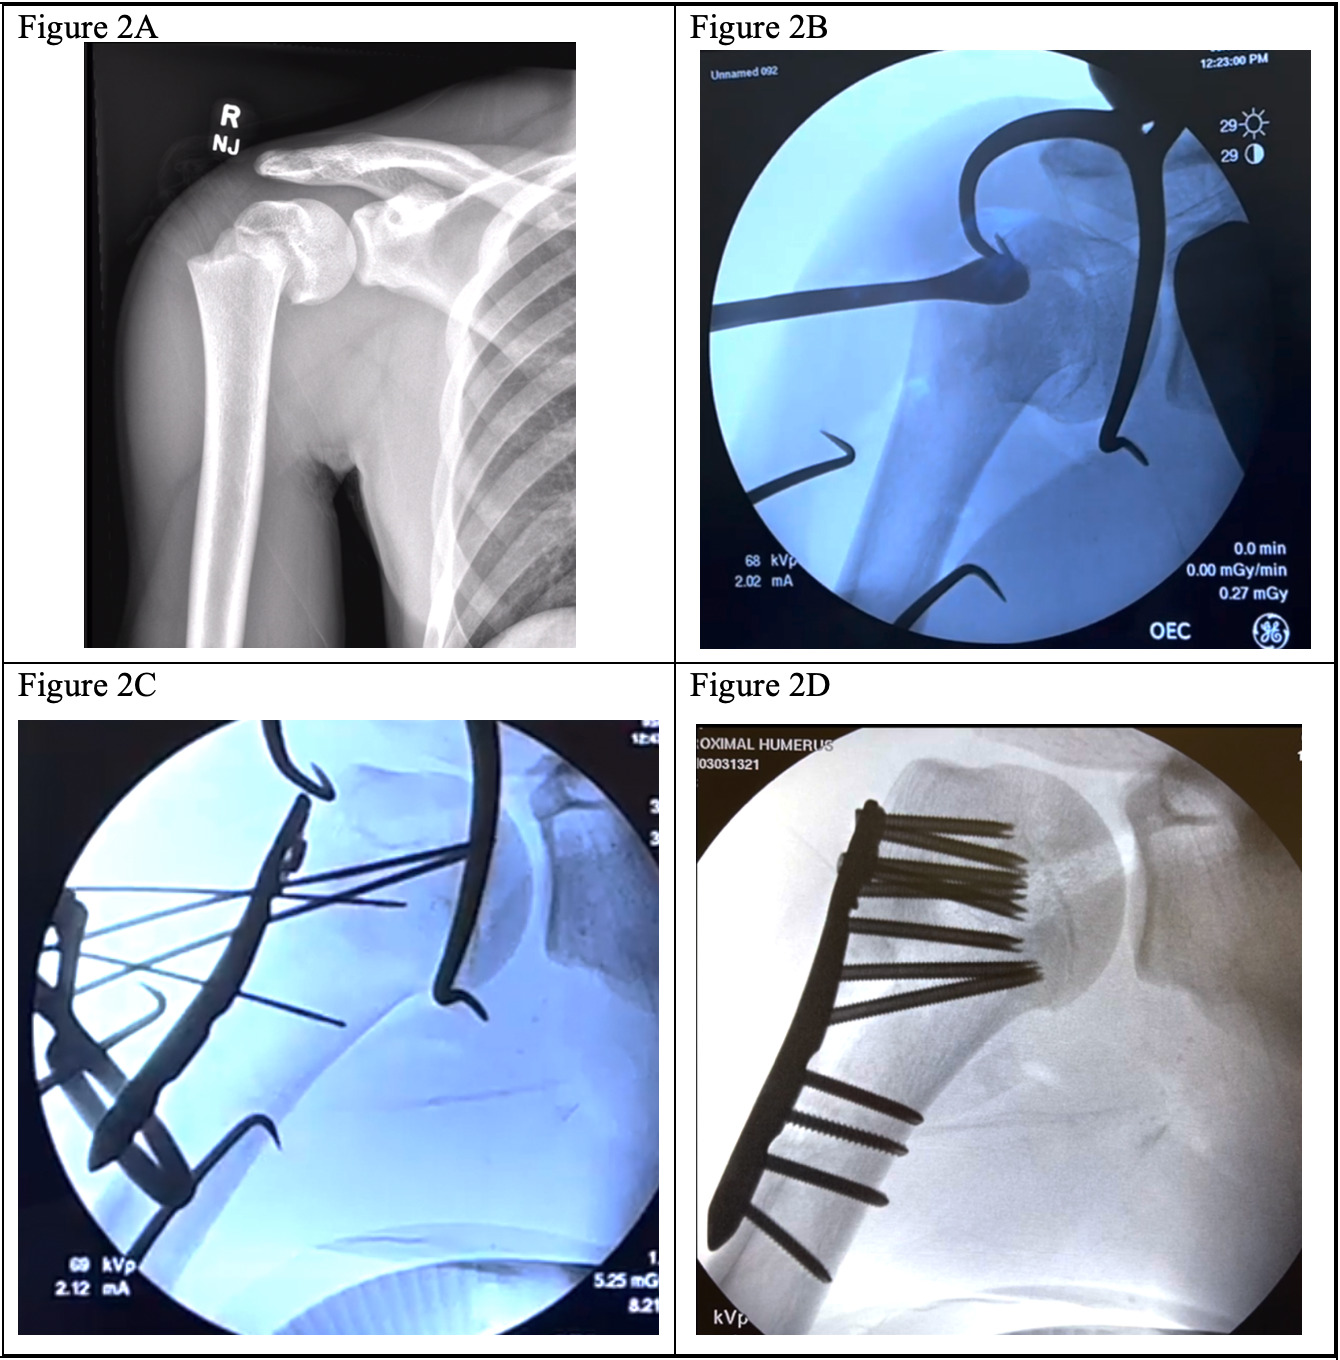

A cobb elevator can then be placed within the fracture site to elevate the humeral head relative to the shaft. In contrast, the retention suture in the humeral head is tensioned to provide valgus stress [Figure 2B]. This maneuver can assist in correcting the varus collapse of the fracture. Once reduced, the fracture can be provisionally fixed with Kirschner wires [Figure 1C]. Alternatively, the plate can be applied to the distal shaft, and the proximal, reduced head can be pinned to the plate. The proximal end of the proximal humerus locking plate is preloaded with heavy sutures to augment the repair by placing sutures through the rotator cuff and any displaced tuberosity fragments post-fixation.

Fixation

The following technique is associated with figures utilizing the proximal humerus anatomic locking plate system manufactured by DePuy Synthes (LCP Proximal Humerus Plate, DePuy Synthes, West Chester, PA). An anatomic locking plate is applied to the lateral aspect of the humerus just lateral to the biceps tendon, medial to the deltoid insertion distally, held in place with Kirschner wires proximally and distally, and alignment is confirmed using C arm fluoroscopy [Figure 2C]. Proper plate positioning is important to prevent functional limitations or damage to surrounding structures. Therefore, the plate should be positioned inferior to the superior aspect of the greater tuberosity and posterolateral to the bicipital groove to prevent shoulder impingement or injury to the biceps tendon, respectively.5

Initial screws placed in the proximal humeral head can be non-locking conical screws that allow compression of the humeral head to the plate and further minimize residual varus alignment. The remaining proximal screws are placed locking until the humeral head is filled with screws. Care must be taken to avoid violation of the articular surface. Final distal shaft screws are then placed as desired in either a locking or non-locking fashion. If preferred, the most proximal conical screws can also be switched to a locking screw. The final calcar screw is placed with the goal of placing as close to the inferior aspect of the head as possible to maximize construct stability and mitigate the risk of varus collapse of the humeral head. In a patient with open growth plates, proximal screws are left intentionally short to preserve the integrity of the physis [Figure 2D]. In skeletally mature patients, the goal is to achieve an appropriate screw length that will capture subchondral bone.